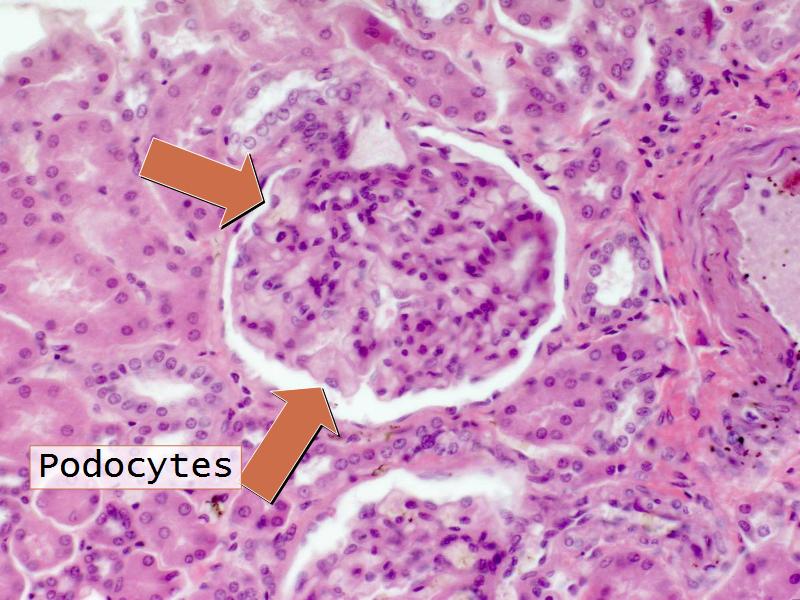

- Kidney = cuboidal, squamous

- Structure of the nephron and collecting tubules

- The renal corpuscle